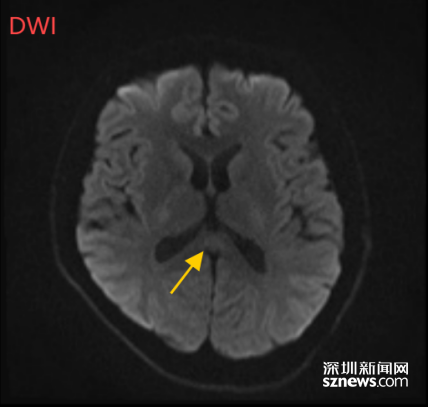

多管齐下的治疗让董先生恢复很快,入院4天后,董先生的不适感消失,神志完全恢复,讲话正常,没有幻觉和视物不清;入院5天,丢失的记忆又找了回来(入院时的董先生失去了前面几天的记忆)。

(董先生的5月9日影像结果显示,胼胝体压部病变好转)

“找回记忆”的董先生告诉医生,4月28日自己曾出现过咳嗽、咽喉痛等感冒症状,只是自服了一点感冒药。因此,董先生的病症还可能是病毒感染引起的,幸好医生已及时进行了抗病毒治疗。

经过治疗,董先生出院时手不抖,走路不晃了,记忆力和计算力也回到患病前的水平。